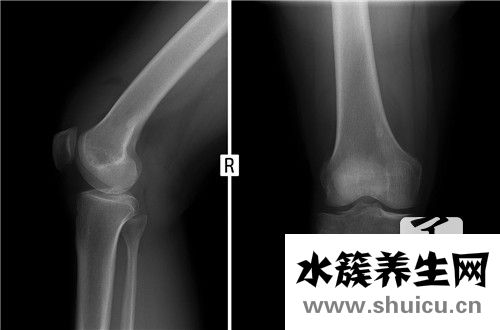

練完瑜伽健身,有些人會感覺膝關(guān)節(jié)疼痛,這要考慮兩個因素。第一,膝關(guān)節(jié)本身可能有問題。比如這些長期過度勞累的人會出現(xiàn)半月板磨損,然后瑜伽健身會加重?fù)p傷進(jìn)而疼痛。另外考慮/123455。...

半月板是膝關(guān)節(jié)的一塊骨頭。在這方面,骨骼已經(jīng)被覆蓋,小腿和大腿的骨骼相互連接,給大家一個很好的固定效果。骨頭這方面雖然看起來微不足道,但功效卻是獨(dú)一無二的,至關(guān)重要,半月板也會受損,使每個人的人...